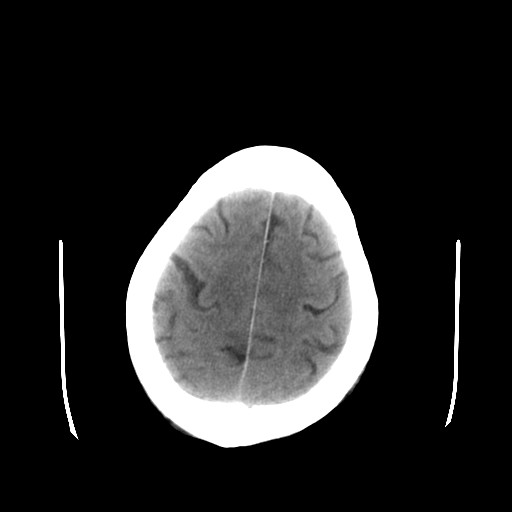

患者,男,70岁,清晨(10小时前)无法自行起床,家人无法唤醒,现昏迷,大小便失禁

左颞枕叶交界区可见类圆形高密度区,边缘可见环形更高密度影,并夹杂有点状钙化影,占位效应明显,未见明显水肿影,考虑脑膜瘤出血

肿快呈以等密度为主的等高密度影,占位效应不是很明显,只是左枕角受压,肿块内侧似有低密度改变.

单纯出血吸收应该从周边开始,

1脑膜瘤

2血管畸形

左颞枕叶交界区可见类圆形高密度区,边缘可见环形更高密度影,侧脑室后角明显受压而周围未见明显水肿.考虑脑膜瘤伴出血可能性大不排外血管畸形.建议mr进一步检查.

左侧颞枕叶交界区见类圆型等高密度混杂影,边缘可见高密度影环绕,同侧侧脑室后脚受压变形,周边围见明显水肿影. 结论:脑膜瘤首先考虑.

左颞枕叶交界区的类圆形高密度区首先考虑脑膜瘤卒中,病人左侧小脑半球的还有多个囊性低密度,要考虑同时伴有梗塞的可能。